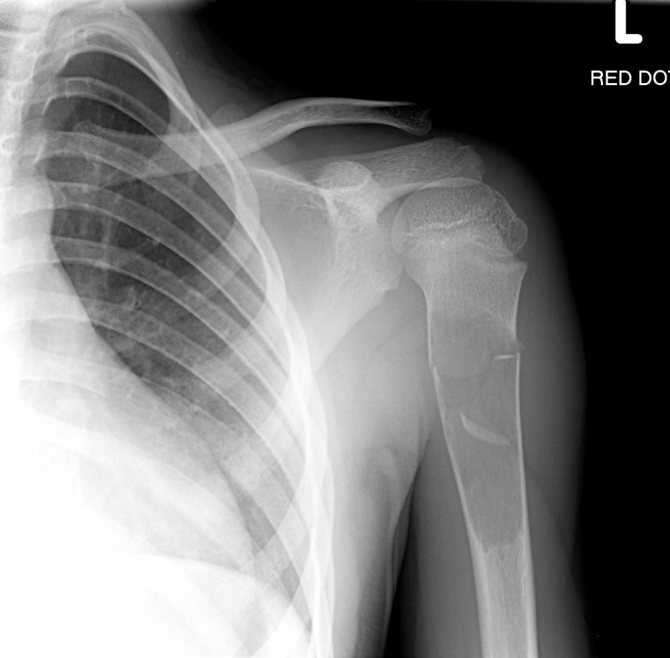

С помощью исследования можно обнаружить и дифференцировать следующие патологии:

- вывихи и подвывихи;

- трещины плечевой кости, лопатки, ключицы;

- переломы (со смещением и без);

- остеопороз;

- плечевой артрит;

- новообразования.

При многих травмах наблюдается рентгенонегативный период, при котором поражение на начальной стадии локализуется только в мягких тканях и не обнаруживается на обычном рентгеновском снимке.